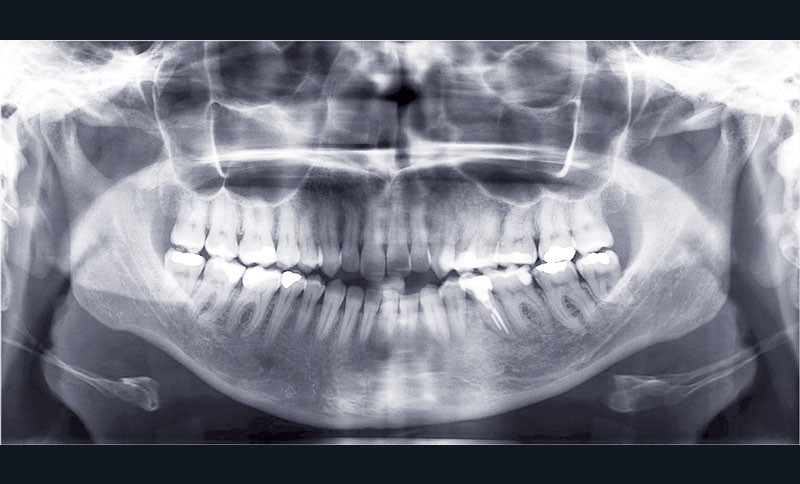

Cas n° 1

Il a été décidé de mettre en œuvre une thérapeutique avec brackets vestibulaires Damon afin d’optimiser l’expansion des arcades, la fermeture de la béance et la réduction du sourire gingival latéral qui perturbe l’esthétique du sourire de la patiente.

La patiente demande des attaches céramiques et nous trouvons un compromis en lui proposant un appareillage Insignia Damon Clear au maxillaire et Damon métallique à la mandibule.